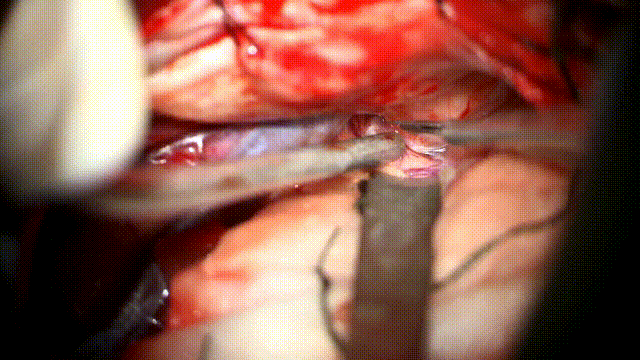

临时阻断M1段,充分分离动脉瘤瘤颈并夹闭

使用AR增强现实荧光,可在自然解剖结构下看到动脉瘤无荧光信号通过,瘤颈被完全夹闭

对于大脑中动脉破裂动脉瘤的手术,我们强调动脉瘤出血的控制,AR增强现实荧光技术相较于传统黑白荧光技术,荧光信号可以和显微镜下视野实时重叠,看到非常清晰直观的荧光影像,判断动脉瘤是否完全夹闭,载瘤动脉是都通畅。整个过程中如果出血的话可以直接在显微镜下一边处理一边看荧光显影的情况,增加了手术的安全性。